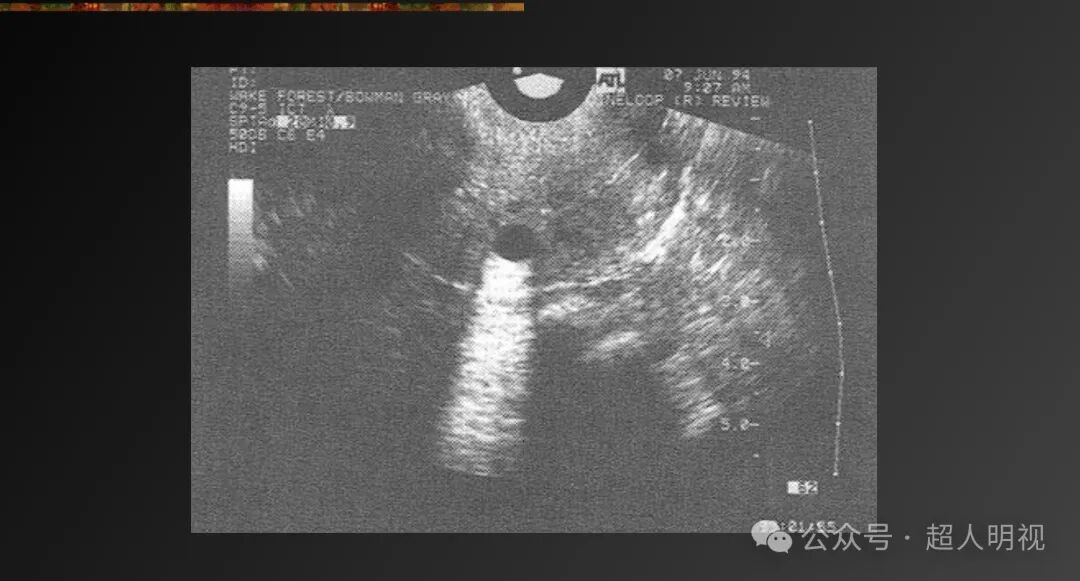

- 镜面伪影(强反射界面另一侧显示镜像结构)

- 折射伪影(声速差异导致结构位置显示错误)

彩超伪像是什么超声伪像_https://www.jmylbn.com_新闻资讯_第8张